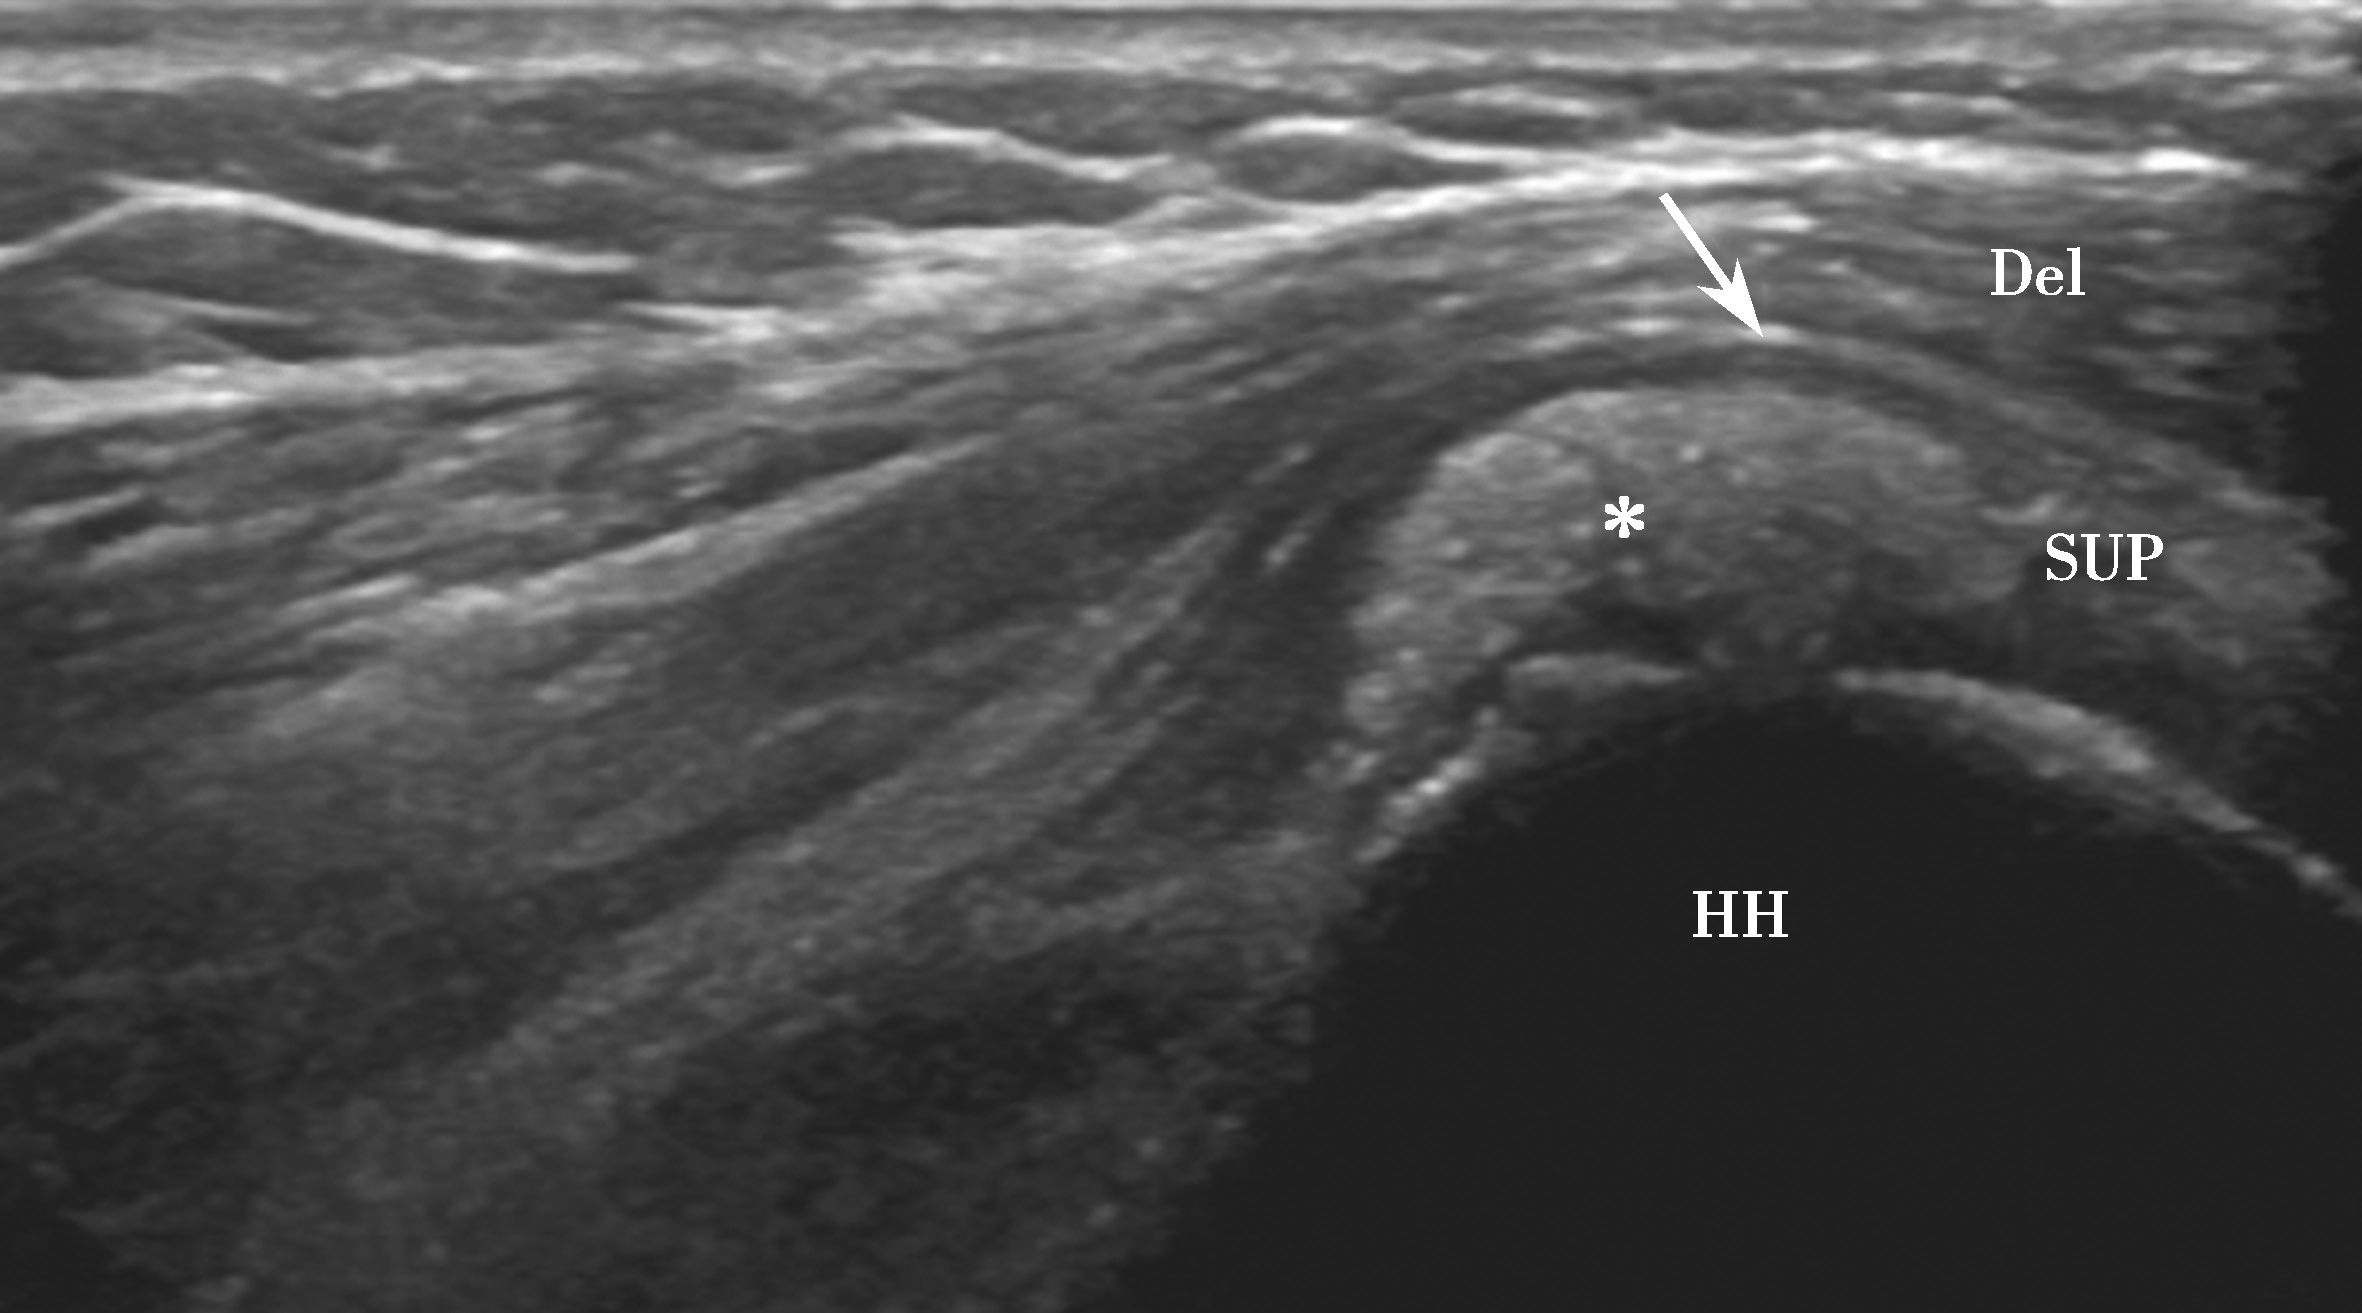

▲ 图2-2-4 超声引导下肩袖钙化性肌腱炎介入治疗超声图

短箭头:钙化灶;长箭头:穿刺针